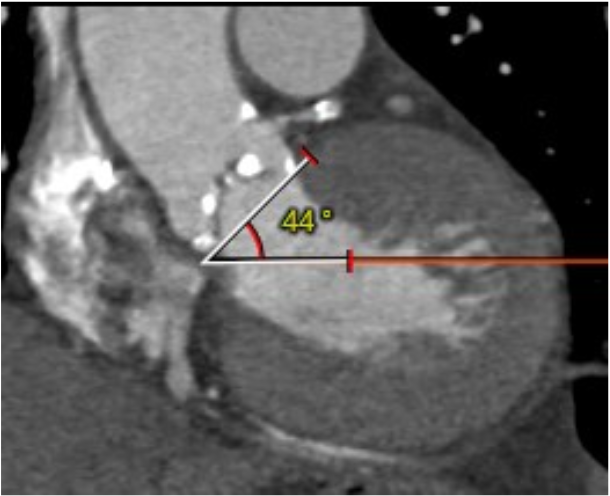

心室角度44°: